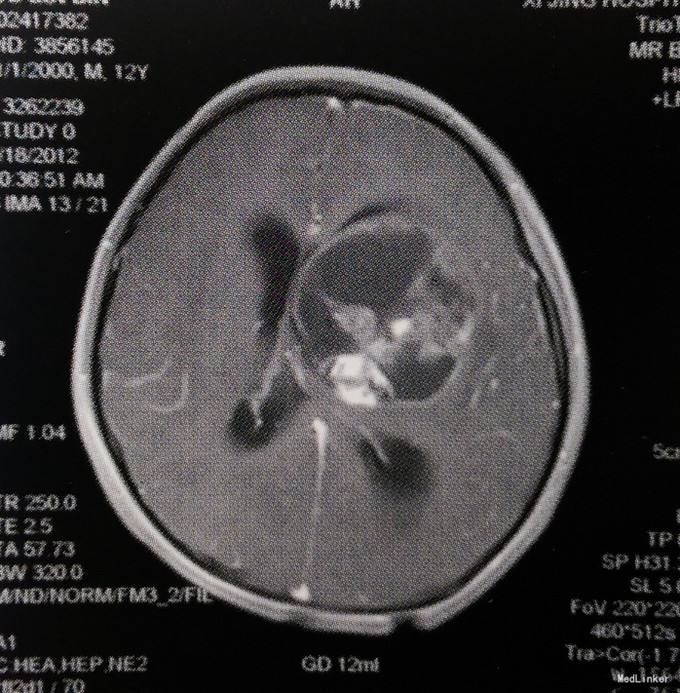

体格检查:意识呈昏睡状,查体不配合,双侧瞳孔等大等圆、对光反射迟钝,四肢肌力III级,肌张力轻度增高,右侧Babinski征阳性,颈抵抗阳性。 头颅MRI检查:左侧基底节区及丘脑占位性病变,呈囊实性混杂成分,边界欠清,实性成分呈明显不均匀强化,考虑生殖细胞瘤或胶质瘤可能性大;左侧侧脑室明显受压变形,中线向右侧移位;幕上梗阻性脑积水。